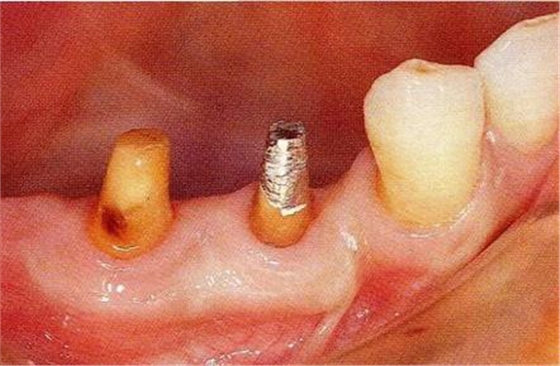

圖17-4(左),5 (右)▲術(shù)后9年的口腔內(nèi)照片和X線片,牙槽嵴平坦化,牙周探診數(shù)值很小。